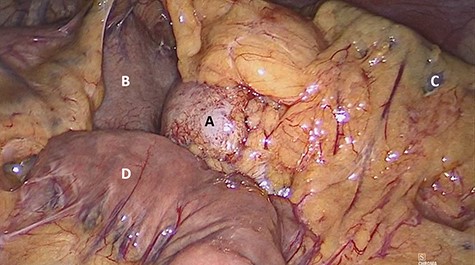

The patient underwent laparoscopic distal pancreatectomy with splenectomy (Figs 7 and 8) with the same surgical team. The patient had an uneventful postoperative recovery and was discharged within 48 hours.

Laparoscopic view of (A) nodular lesion, (B) stomach, (C) spleen and (D) small intestine.